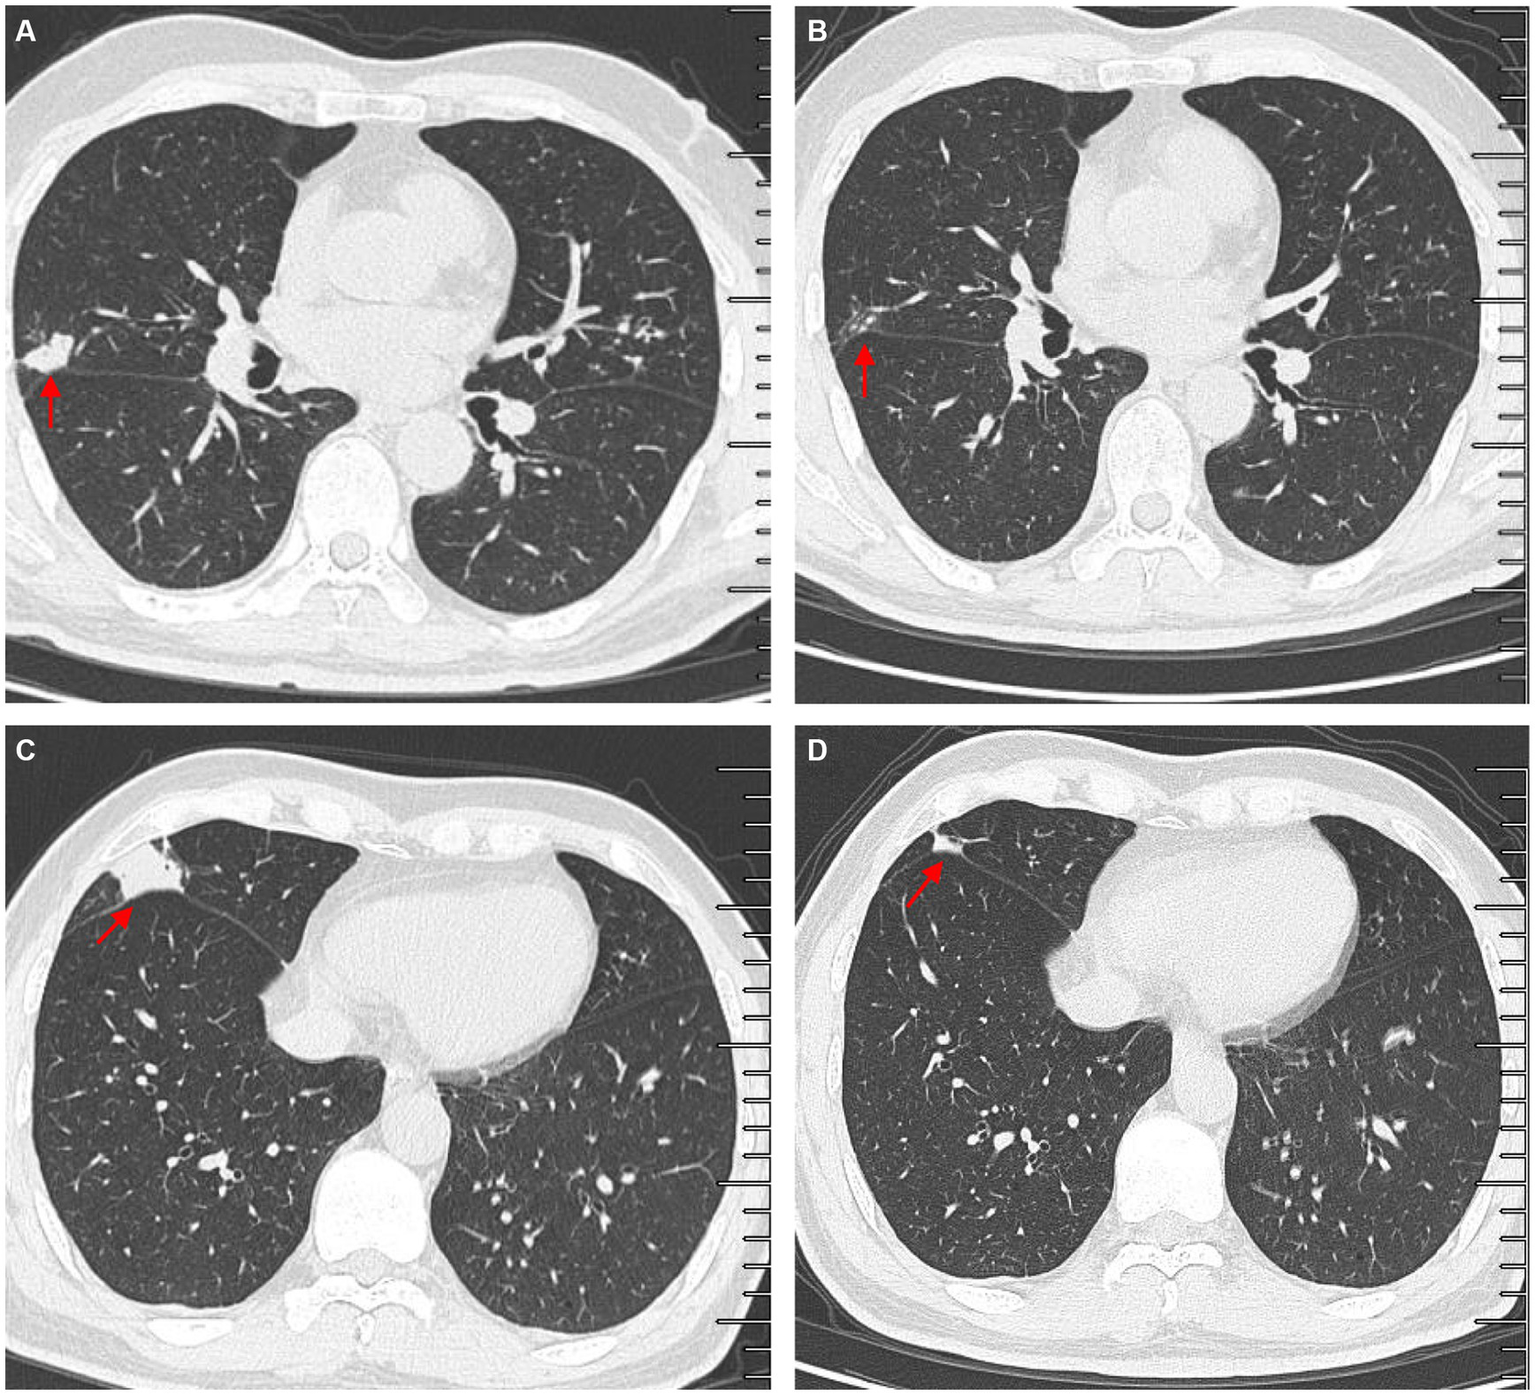

A 61-year-old man presented with bilateral lung nodules in chest roentgenograms (Figure 1A) during his routine health examination in January 2019. The bilateral lung nodules remained stable during subsequent regular outpatient reexaminations in February 2019, December 2019, and December 2020. Particularly, this patient showed no clinical symptoms throughout this period. However, in July 2021, the patient was admitted to our hospital due to hemoptysis. He did not display symptoms commonly associated with infection, such as fever, dyspnea, pyrosis, night sweats, or weight loss at that time. Additionally, the physical examination results were also normal. All laboratory tests of the patient, including peripheral blood count, renal and liver functions, indirect immunofluorescence test for antinuclear (ANA) antibodies, rheumatoid factor test, anti-cyclic citrullinated peptide test, anti-extractable nuclear antigen test, lymphocyte subtype test, urine test, and stool test showed normal results. The patient underwent a chest computed tomography (CT) scan, revealing multiple small nodules in both upper lobes and ground glass opacity in the right upper lobe (Figure 1B). The nodules were found to be similar in size to the ones found in the original CT scan from January 2019, but ground glass opacity was observed. Subsequently, the patient underwent bronchoscopy examination, and bronchoalveolar lavage fluid (BALF) samples were collected for further pathogen analysis. The results of the acid-fast bacilli (AFB) test and GeneXpert MTB/RIF test for sputum and BALF were all negative. The patient then received antibiotics treatment with moxifloxacin, while he did not show hemoptysis during his stay at the hospital. The patient did not show any symptoms throughout the 5-day course of antibiotics treatment and was subsequently discharged from the hospital.

Figure 1

High-resolution chest computed tomography (CT) scan results from different periods. (A) CT scan results from different layers taken on 14 January 2019. The multiple small nodules (red arrow) in the right upper lobe, left upper lobe, and right middle lobe. (B) The patient underwent a CT scan of the chest on 7 July 2021, which showed ground glass opacity in the right upper lobe (red arrow) and multiple small nodules in both upper lobes (red arrow). (C) Outpatient reexaminations using a repeat CT scan on 19 August 2021 revealed an increase in the size of multiple small nodules in the upper and middle lobes (red arrow).

Another outpatient reexamination on 19 August 2021 using a repeat high-resolution chest CT scan revealed a noticeable increase in the size of the multiple small nodules in the upper and middle lobes of the lung (red arrow) (Figure 1C). A chest CT-guided lung biopsy was performed. The histopathology (right lung biopsy) showed the alveolar tissue, local lymphocyte infiltration, granulomatous lesions, scattered Langerhans giant cells, some fibrinoid exudates along with no caseous necrosis. The result of the tissue acid-fast staining was negative (Figure 2). As such, a second bronchoscopy was performed, and BALF was collected for pathogen testing. However, both acid-fast bacilli test and GeneXpert MTB/RIF test results for BALF were negative. Particularly, this patient still experienced no clinical symptoms of infection during this time. On 24 August 2021, the lung tissue and BALF of the patient were subjected to mNGS testing, and 23 reads (Figures 3A,B) and 11,948 reads (Figures 3D–F) of MAC were identified within 3 days. Moreover, the MAC infection was confirmed again through a BALF culture test conducted 20 days later. The patient was then treated with a combination of ethambutol (25 mg/kg three times per week), rifampicin (600 mg three times per week), and azithromycin (500 mg three times per week) after breakfast for 6 months. Notably, the patient did not experience any additional symptoms during these drug treatments. It is also worth noting that no drug-related adverse reactions were observed throughout the treatment period. Moreover, a significant decrease in nodule size was observed in a high-resolution chest CT scan which was performed 2 months after the aforementioned combination therapy (Figure 4).